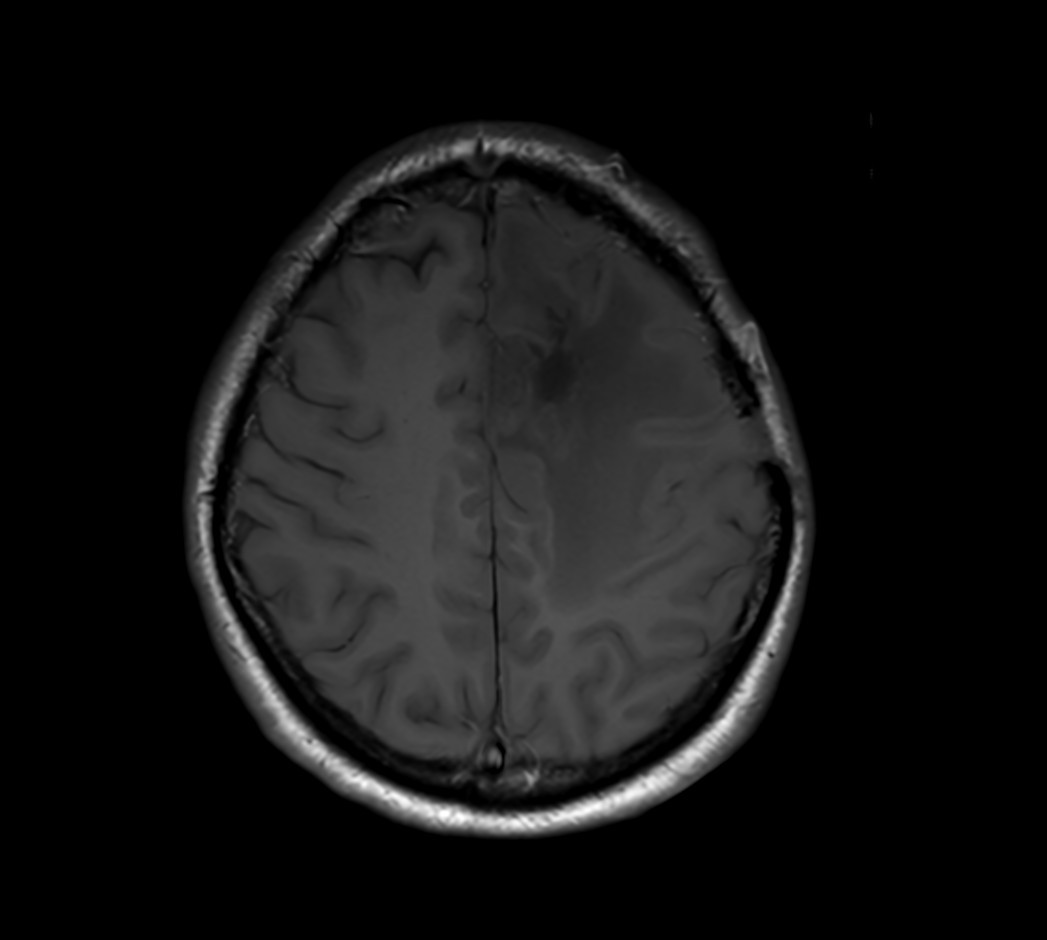

SmartSpeed Precise imaging for brain with glioblastoma

Kyushu University Hospital Japan